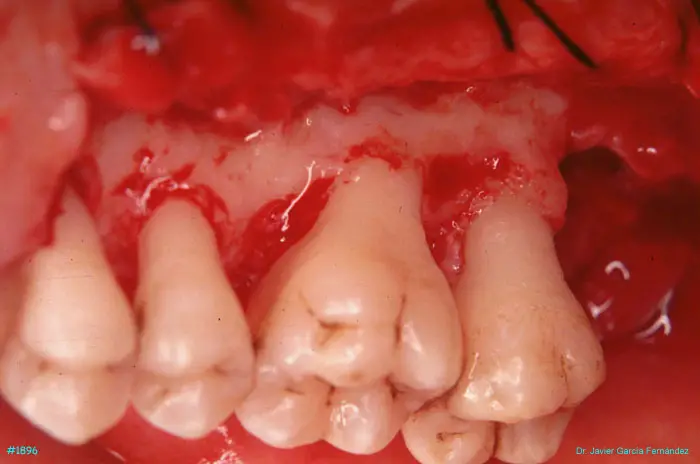

image 42